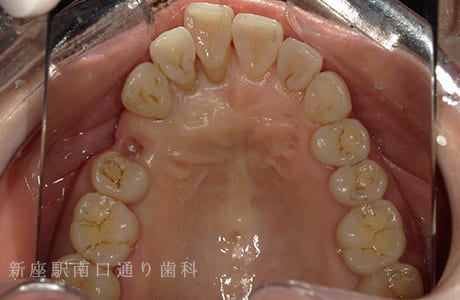

CASE.02

左上のフルジルコニアブリッジで

修復した症例

-

- 主訴

- 歯がないところを治したい

- 治療法

- 左上にフルジルコニアブリッジで修復

- 治療期間

- 1ヶ月半

- 費用

- ¥240,000(税込)

【リスク・副作用】

過度の咬合や衝撃で割れることがあります。治療直後は歯や歯茎に一時的な違和感や痛みが出ることがあります。